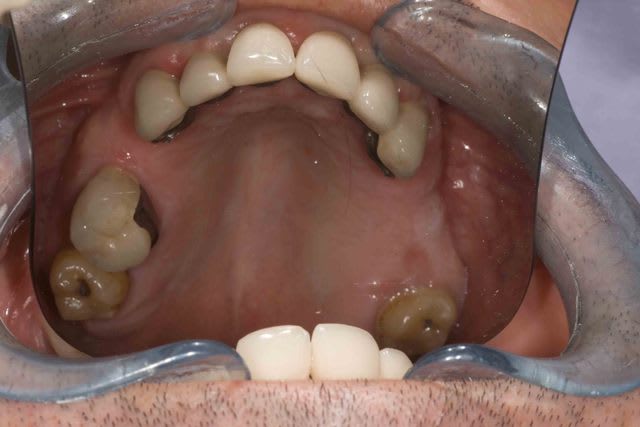

Concernant les attachements j'ai une preference pour les attachement extra coronaires type VKS . Plusieurs forces differentes, tres facile a changer et pas trop chere. Par contre commme il s'agit d'extracoronaires je solidarise toujours les dents afin de limiter l'effet balancoire sur les couronnes. C'est pour cette raison que sur 45 j'ai mis un crochet et non pas un attachement car la dent est seule.

Pour le reste 11-13 solidarisés, 21 23 solidarisé, 31 unitaires et 32-34 solidarisé.

J'avais oublié la pano de départ + la photo des fraisages et attachement .